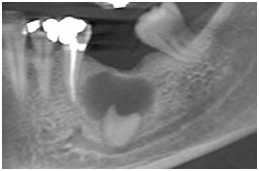

• Avaliar a relação de dentes inclusos com acidentes anatômicos

Relação dentes inclusos X acidentes anatômicos Relação dentes inclusos X acidentes anatômicos